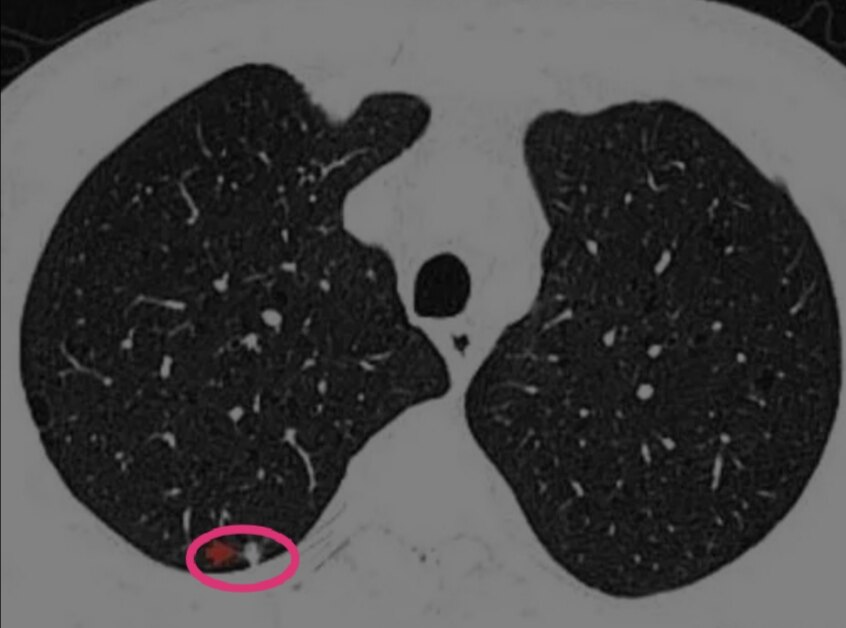

看下这个结节。男性,重度吸烟史,肺气肿背景,CT发现右上肺后段胸膜下,实性5mm的结节。

右下肺后段肺部微小实性结节